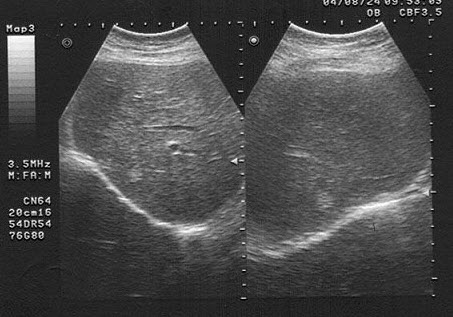

女,40岁,有时右上腹隐痛2年余。结合超声声像图,最可能的诊断为()

A.肝血管瘤

B.肝脓肿

C.小肝癌

D.转移性肝癌

E.肝囊肿